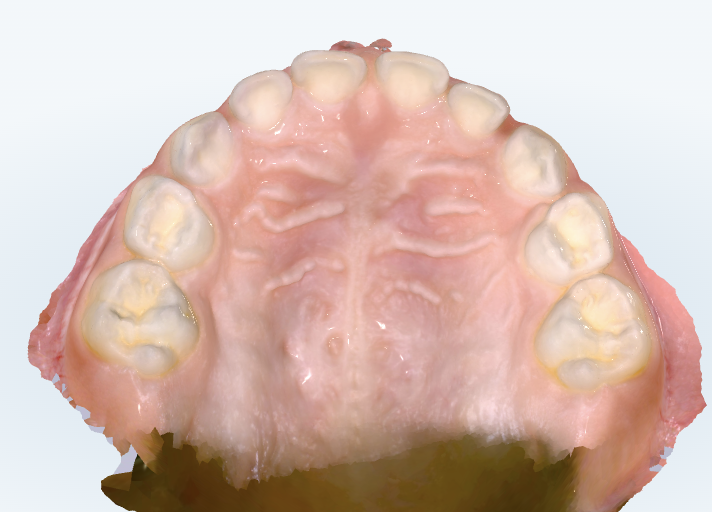

初診時の画像診断

上下の歯並びに隙間があります。上の前歯の間の筋もあります。

下の前歯の永久歯が乳歯の内側から生えてきています。